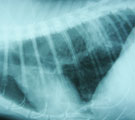

びまん性網状影に加え後葉中央に浸潤影出現 2ヵ月後の入院時。呼吸が荒く食欲元気なし。 LB2D2より気管支鏡にて経気管支生検 検査後2日目元気になり退院。

経過:3年前呼吸荒いとのことで受診あり、浅速呼吸と胸部レントゲンでのびまん性間質影から慢性間質性肺炎と診断しステロイド治療を続けてきた。しかし嘔吐を機会に呼吸困難が起こったので来院した。努力性呼吸あり血液ガス分析にて低酸素血症(PaO2 69.1mm Hg)を示した。胸部レントゲンではびまん性網状影に加え左後葉中央部に浸潤影が出現していた。感染の可能性ありステロイドを中断し気管支拡張と抗生剤療法に切り替えた。2ヶ月後、呼吸状態は悪化し低酸素血症も進行した(PaO2 51.9mm Hg)。慢性間質性肺炎の再燃の可能性あり、浸潤影の原因解明のため気管支鏡にて気道の観察と浸潤影領域の生検を施行した。気道粘膜全体には異常がみられなかった。生検は透視下にてLB2D2に慎重に鉗子を挿入し行った。3回繰り返した。白色粘液状物が採取されたが細菌・真菌は検出されず、細胞診ではわずかの炎症細胞と気管粘膜上皮のみで腫瘍性変化はみられなかった。浸潤影は粘液栓によるもので、呼吸状態悪化はステロイド中断による間質性肺炎の再燃と考えられた。検査後、粘液栓を取り除いたためか全身状態は良好となり2日目に退院となった。その後、ステロイドと去痰剤投与を始め元気食欲が極めて改善した。